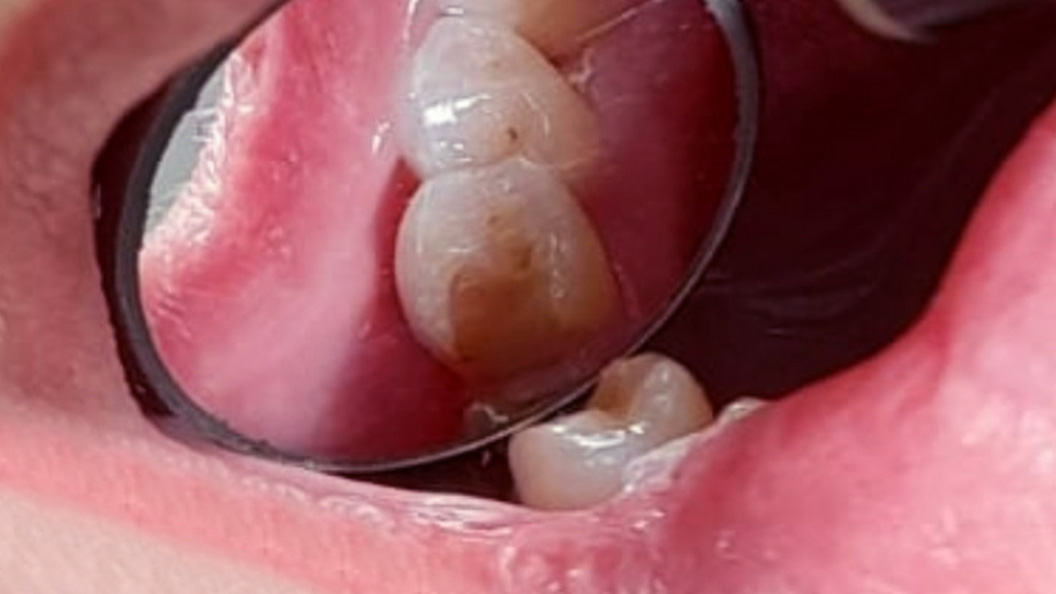

Пациентка обратилась в «Стоматологию Комфорта» с жалобой на образование полости в зубе 4.5, а также острую, быстро проходящую боль от холодного. Врач Похилько Надежда Геннадьевна провела осмотр и обнаружила хронический глубокий кариес нижнего премоляра. Принято решение провести лечение зуба и пломбирование с помощью композитного материала Эстелайт.

Глубокий кариес — это крайняя стадия кариозного поражения, при котором повреждены более 50% твёрдых тканей зуба. На этом этапе пульпа защищена лишь тонкой прослойкой дентина и в любой момент может быть поражена. Если немедленно не приступить к лечению, неизбежна потеря зуба, а также возможно развитие пульпита, пародонтита и других заболеваний полости рта.